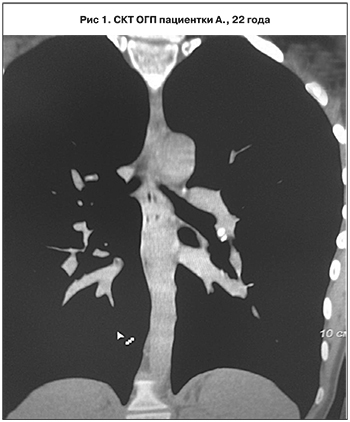

Клинический случай.

Студентка А., 22 года. Контакт с больными туберкулезом не установлен. БЦЖ – 2 рубчика 0,5 и 0,6 см. Симптомы интоксикации отсутствуют. Флюорография проводилась ежегодно (2012–2016 гг.), патологических изменений не выявлено. На учете у врача-фтизиатра не состояла. Проба с АТР – 23 мм с везикулами, отеком предплечья. На СКТ ОГП – 2 кальцината размерами 4–5 мм в бронхопульмональной группе лимфатических узлов слева (рис. 1).